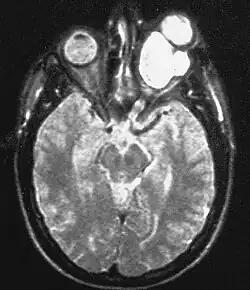

Magnetic resonance image of a large retrobulbar optic nerve tumor causing massive proptosis

Optic nerve gliomas are diagnosed using magnetic resonance imaging (MRI) and CT scans.[5] The tumor adopts a fusiform appearance, appearing wider in the middle and tapered at the ends.[5] Enlargement of the optic nerve along with a downward kink in the mid-orbit is usually observed.[5] While CT scans allow for optic nerve evaluation, MRI allows for intracranial evaluation to observe if the tumor has extended to other regions such as the optic chiasm and hypothalamus.[6]